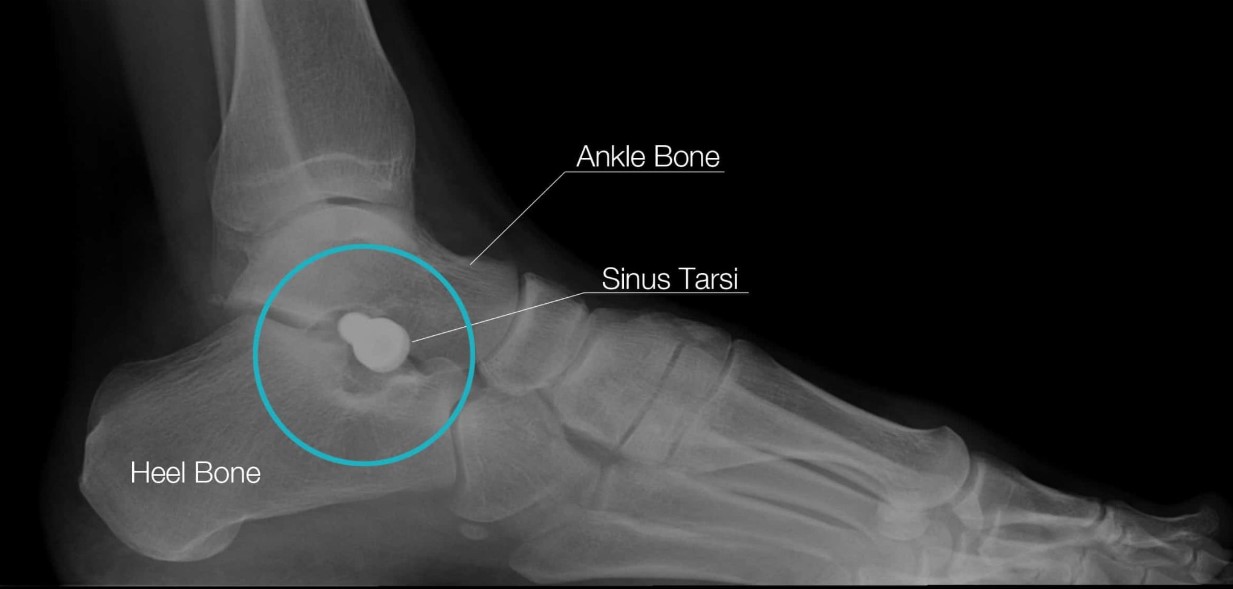

HyProCure is place in the naturally occurring space between your bones to instantly realign and stabilize the hindfoot. It will not penetrate or be implanted into your bones.

HyProCure corrects irregular foot form and alignment. The procedure uses an incision in your arch to correct the misaligned bones in your foot, allowing your bones to move freely again. HyProCure also reduces pressure on nerves, which can cause pain and inflammation.